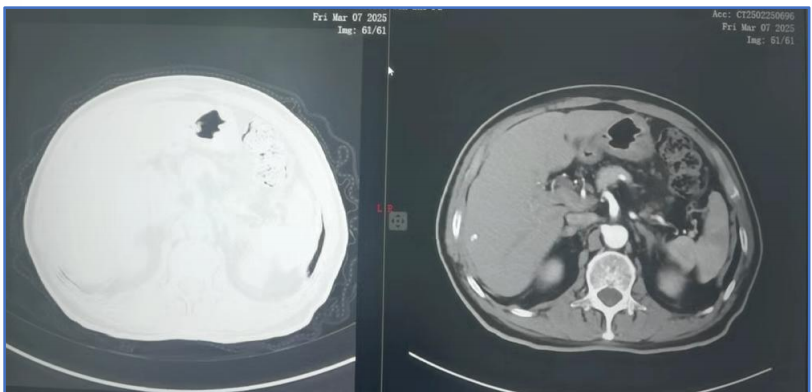

胸部影像学(PET/CT): 提示右肺门淋巴结、纵隔(4R)转移,左侧肺门及双肺叶间密度较高淋巴结。

1.png

肺恶性肿瘤(右上 鳞癌 cT1N2M0 IIIA期)。